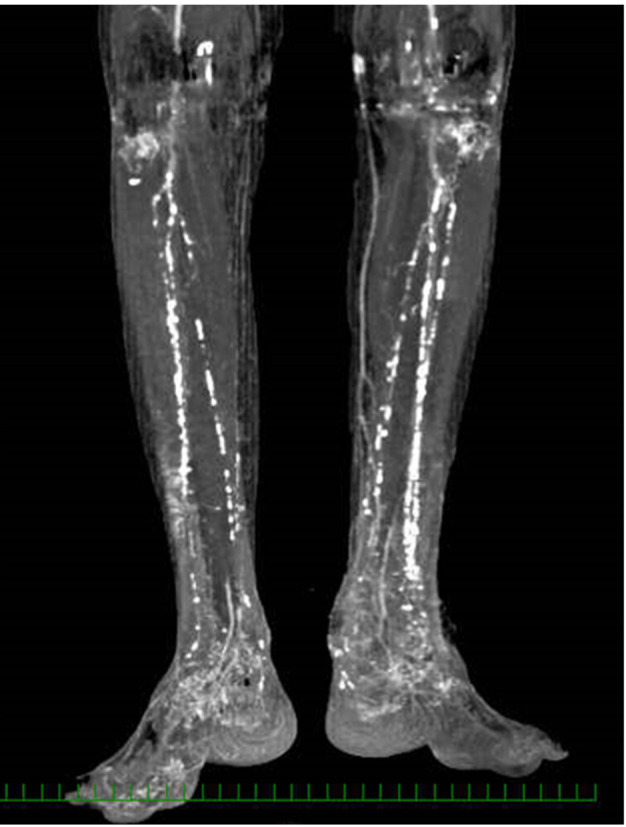

Background: Chronic limb-threatening ischemia is a condition of the lower extremities that requires therapeutic intervention. It is characterized by ischemia, tissue loss, neuropathy, infection, and risk of amputation.

Case: An 82-year-old woman with a history of bilateral total knee arthroplasty and rheumatoid arthritis underwent a left ankle arthroplasty. Wound healing was delayed, and chronic limb-threatening ischemia was diagnosed. When endovascular therapy was found ineffective, novel low-density lipoprotein apheresis was initiated. Pedicle flap and split-thickness skin grafting were performed to save the affected limb. However, skin necrosis progressed, and the patient underwent left lower limb amputation 17 days after ankle arthroplasty. The stump included a skin graft area, and the decision to fabricate a prosthetic leg was difficult because of the patient's advanced age, rheumatoid arthritis, and poor upper limb function. However, her cognitive function, muscle strength, and joint range of motion were good. No sign of wound infection was observed, and the patient was able to walk before surgery. Therefore, we decided to fabricate a prosthetic leg. Seventy-five days after amputation, the patient achieved independent walking using a cane and a silver-wheel walker.

Discussion: The benefit of novel low-density lipoprotein apheresis helped our decision to fabricate a prosthesis when uncertainty existed about the maturity of a recent amputation in an elderly patient with chronic limb-threatening ischemia. The patient successfully achieved a prosthetic gait under challenging conditions.